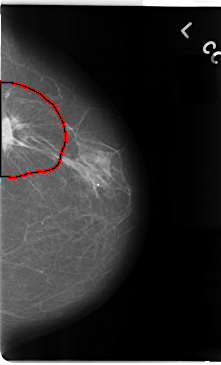

C_0079_1.LEFT_CC

LEFT_CC LINES 4744 PIXELS_PER_LINE 2872 BITS_PER_PIXEL 12 RESOLUTION 50 OVERLAY

FILE: C_0079_1.LEFT_CC.OVERLAY

TOTAL_ABNORMALITIES 1

ABNORMALITY 1

LESION_TYPE MASS SHAPE IRREGULAR MARGINS SPICULATED

ASSESSMENT 5

SUBTLETY 5

PATHOLOGY MALIGNANT

TOTAL_OUTLINES 1

BOUNDARY